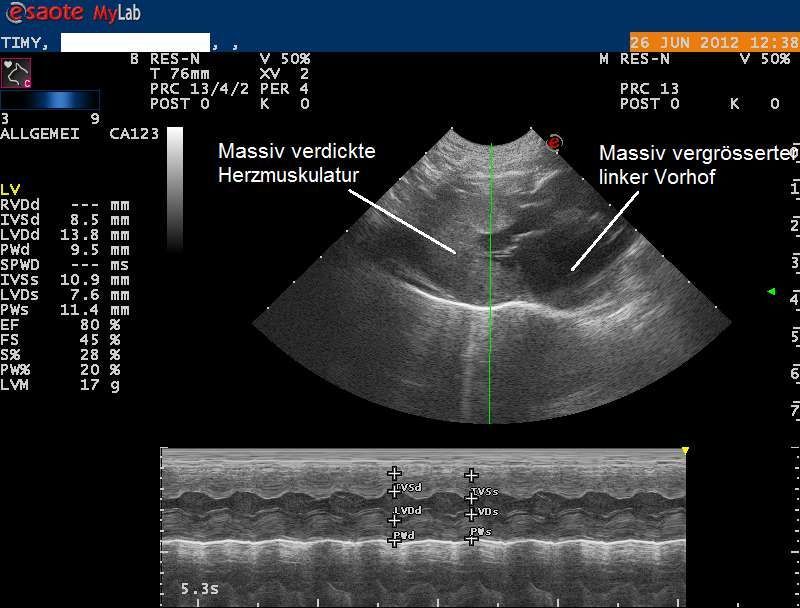

Die Röntgenbilder weisen auf eine Herzerkrankung hin, welche zum Verschluss der Körperschlagader geführt haben könnte. Das Herz wird mittels Ultraschall genauer untersucht, und es zeigt sich, dass die Muskulatur der Herzkammern sehr stark verdickt und die Vorhöfe stark erweitert sind. Eine Diagnose einer Hypertrophen Kardiomyopathie (HCM) wird gestellt.